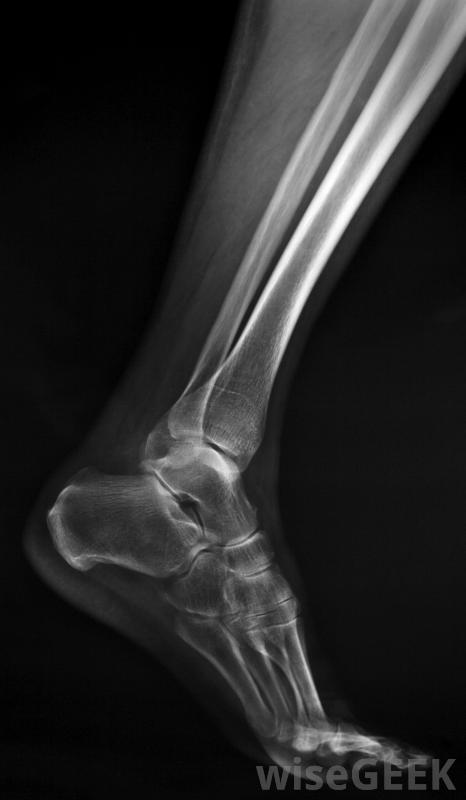

如何治療撕脫性骨折可能取決于幾個因素,其中包括骨折患者的年齡和損傷的嚴重程度。在許多情況下,撕脫性骨折可能不需要太多的治療,除了醫生的診斷和規定的休息時間外。當骨折代表更嚴重的損傷時,可以采用更廣泛的方法來治療撕脫骨折。石膏通常用于治療撕脫性骨折。當試圖評估如何治療撕脫性骨折時,它有助于了解這種類型的損傷是什么。在這種形式的損傷中,韌帶或肌腱通常是在劇烈的運動中,如投擲或跳躍時,從骨頭上拉出來。當這種情況發生時,韌帶或肌腱,因為它附著在骨頭上,所以可以帶走一塊骨頭如果沒有X光片,不可能知道與撕脫骨折相關的骨骼損傷程度。這種損傷聽起來非常嚴重,但在許多情況下,治療撕脫性骨折的黃金標準是讓人們休息,根據需要使用糖霜來消腫,可能還需要開一些消炎藥來幫助減輕炎癥。休息時間可以持續兩到六周,這取決于損傷的嚴重程度。通常情況下,這足以讓骨骼重新附著并愈合一些醫生計劃在一個設定的時間點進行后續的x光檢查,以確保再次附著成功。對撕脫性骨折進行冰敷可能有助于減輕腫脹雖然上述治療撕脫性骨折的方法在很多情況下都可以使用,但有時需要更大的干預來處理這種損傷。有時當肌腱或韌帶拉傷時,在這個過程中,它會受到嚴重的損傷。這種損傷將使骨骼無法正常地縫合在一起,并可能影響骨折部位的功能。在這種情況下,可能需要手術修復韌帶或肌腱損傷另一個值得關注的問題是當兒童發生撕脫性骨折時。孩子們通常會沿著骨生長板發展這些骨折。當這些骨折影響到生長板時,人們真的擔心骨骼不能正常地結合在一起,這可能會在生長過程中導致畸形。醫生可能會治療撕脫傷在生長板上發生的骨折通過手術來確保愈合是完全促進的,受傷區域不會影響將來的生長。應該注意的是,人們不建議在家里治療任何形式的骨折撕脫骨折可能看起來更為良性,至少在某些時候,如果沒有x光和醫生檢查,不可能知道骨或組織損傷的程度所有懷疑自己骨折的人都應該去看醫生以獲得診斷和正確的治療建議。在某些情況下,有必要進行手術來修復撕脫性骨折過程中受損的肌腱或韌帶。